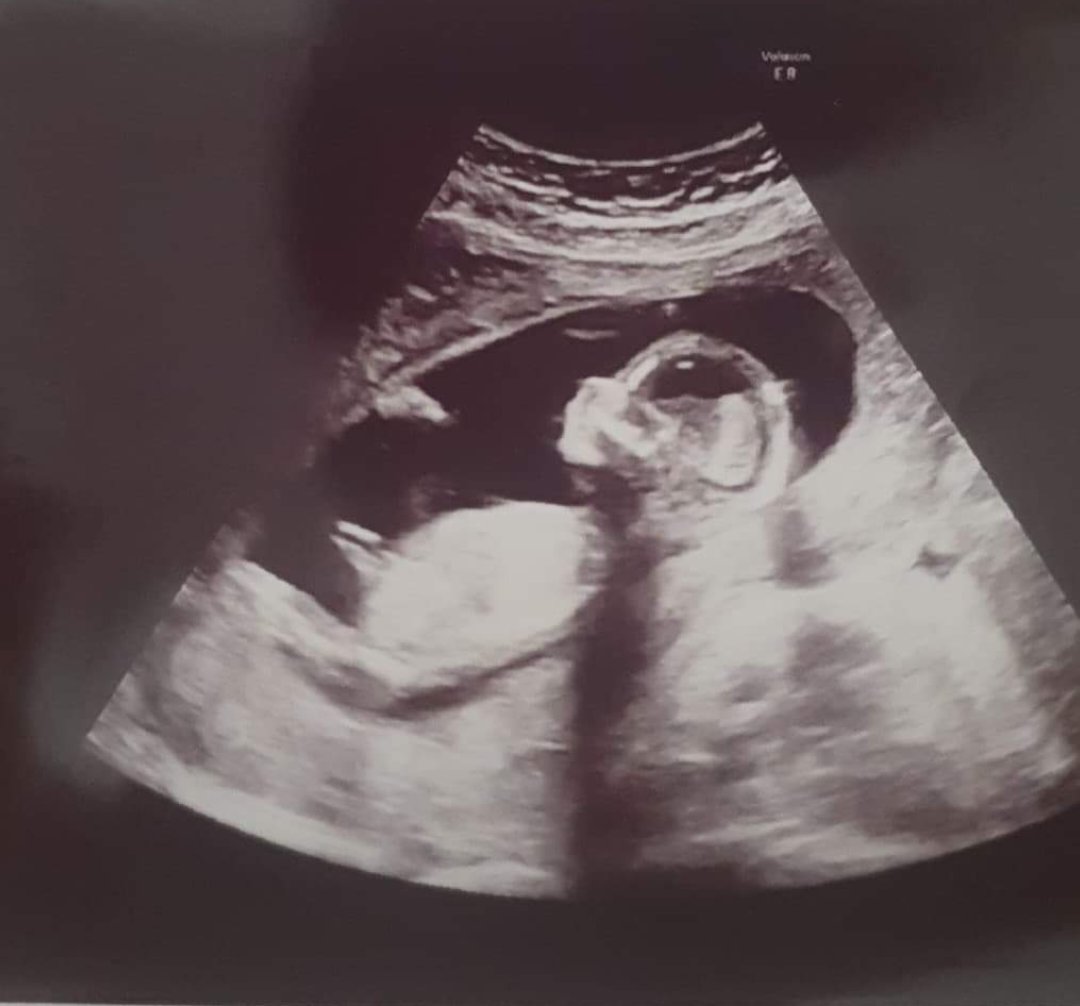

Hej dziewczyny 😊 widzicie tu co się może kryć ? Moja lekarka niby stwierdziła że jeszcze za wcześnie ale akurat tak się dzidziuś ustawił że stwierdziła że może może to dziewczyna bo jest taka malutka kreseczka, ale żeby się nie nastawiać 😊

14 tydz 3 dni 😊

Załączniki

• IMG_20211115_203440.jpg

IMG_20211115_203440.jpg

1,2 MB · Wyświetleń: 204